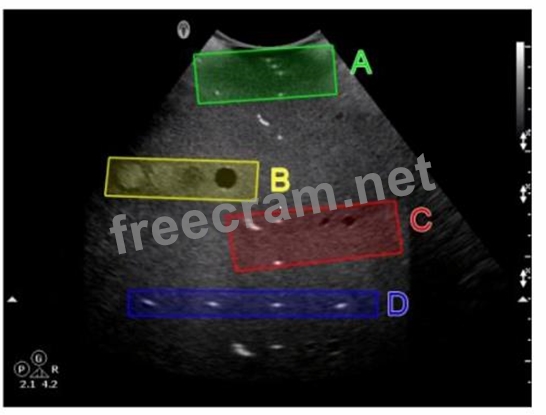

Which target group is used to evaluate transverse distance measurement accuracy in this tissue-mimicking phantom image?

Question 41: Which target group is used to evaluate transverse distance m...